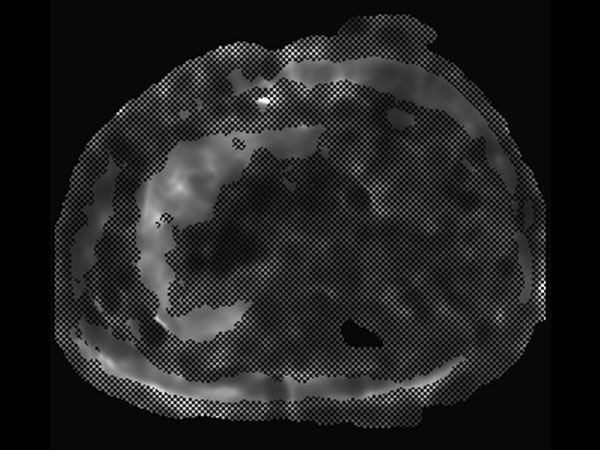

mDIXON Quant (Fat Fraction)